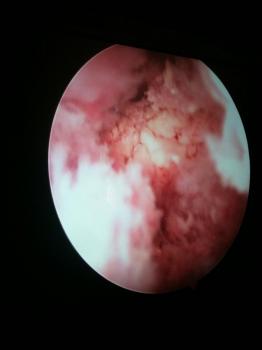

Elle est classiquement réalisée sous arthroscopie, c’est à dire à l’aide d’une caméra vidéo et de petits instruments. Cependant, la chirurgie avec une incision plus importante peut être réalisée dans différents cas.

Le geste chirurgical consiste à enlever une épaisseur d’os sous le dessous de l’os acromion, os surplombant les tendons de l’épaule et les comprimant. On parle de décompression. Plusieurs gestes sont souvent associés lors de la chirurgie : résection ou réparation de la longue portion du biceps (ténotomie), résection de l’articulation acromio-claviculaire, section du ligament acromio-claviculaire, de calcification.